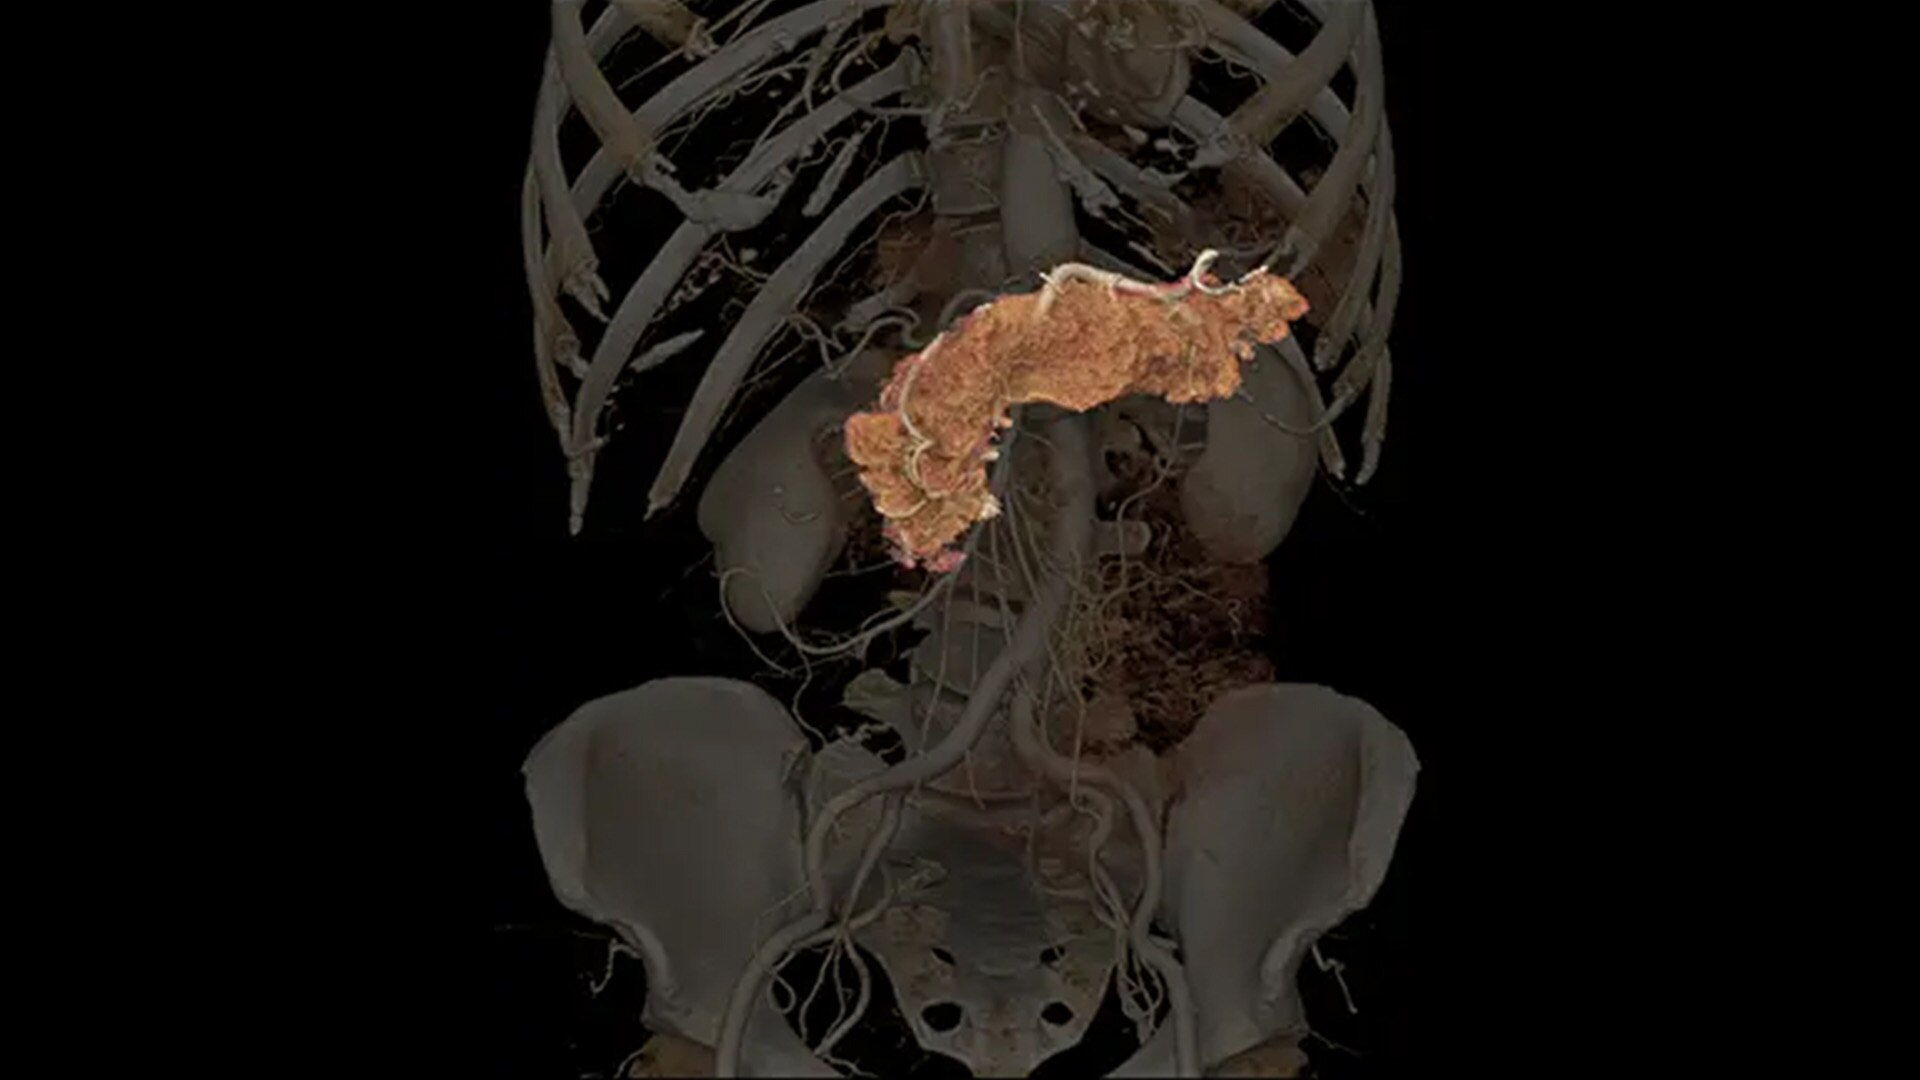

Our advanced spectral imaging capabilities are intended to allow you to experience the difference between seeing and knowing so you can confidently detect, characterize and monitor disease.

Photonova Spectra is also designed to enhance material separation for tissue characterization and disease quantification, bringing potentially greater diagnostic confidence in every acquisition across care areas.

A full range of spectral imaging series is generated natively on console and available for transfer to PACS. The full-fidelity spectral data acquisition is intended to provide native DICOM images and material maps to support clinical diagnosis, with improvements of up to 4x enhanced energy discretization1, 2x higher material map spatial resolution2, and 2x improved iodine detectability3.